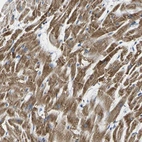

Immunohistochemical staining of human heart muscle shows strong cytoplasmic positivity in myocytes.